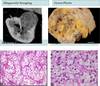

Acute

the kidney is somewhat enlarged, and discrete, yellowish, raised abscesses are apparent on the surface

neutrophilic infiltrate, suppurative necrosis, and abscess formation

Chronic

chronic tubulointerstitial inflammation and scarring involve the calyces and pelvis

parenchyma shows interstitial fibrosis with an inflammatory infiltrate of lymphocytes, plasma cells, and occasionally neutrophils

Xanthogranulomatous pyelonephritis - chronic pyelonephritis characterized by accumulation of foamy macrophages intermingled with plasma cells, lymphocytes, epithelioid cells, and occasional giant cells (associated with proteus)